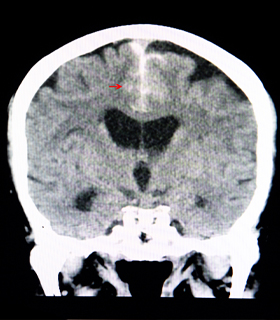

Traumatic Brain Injury (TBI) Surgery

Surgery removes life-threatening clots, hematomas, and skull fractures to treat severe head injuries, enhancing recovery and function.